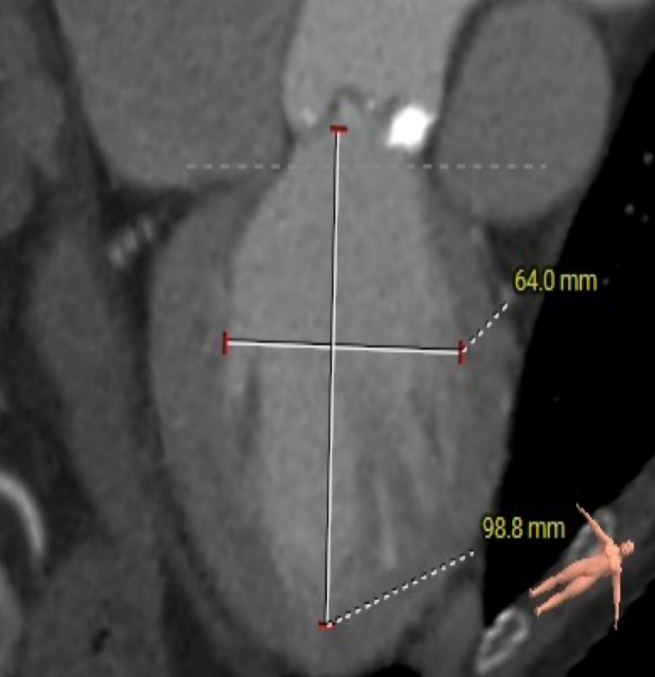

主动脉根部测量

ANNULUS

SOV DIAMETER

LVOT

STJ

瓣环水平夹角

LEFT VENTRICLE

CT数据显示该患者为三叶式主动脉瓣。

主动脉瓣瓣环周长66.2,平均周长径 21.1mm,SOV:32.2mm*36.4mm*34.1mm,瓣叶增厚,瓣上钙化分布不均,主动脉瓣环水平夹角67度,横位心。